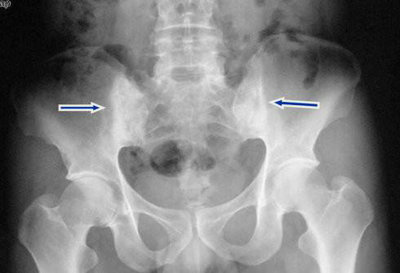

检查结果:ESR增快,为60mm/h,C反应蛋白(CRP)50.5mg/l, HLA-B27(人体抗原白细胞)阴性(-);骶髂关节,椎间小关节和髋关节间隙消失,出现骨性强直;脊柱韧带钙化,形成竹节状外观,骨质疏松严重。

(图:X线片显示其脊柱韧带钙化,骶髂关节强直)